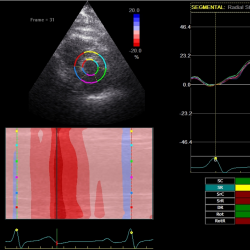

2D-echocardiography measurement was performed at rest in the left lateral decubitus position, using the Vivid 7 device (General Electrical-Vingmed Ultrasound AS, Horten, Norway) with 3.5 MHz transducers. Strain analysis was done by one investigator who was blinded to the results of the CAA examinations by using automated software Echo-PAC (GE Healthcare). The examination included standard measurements: left ventricular posterior wall (LVPW), left ventricular interventricular wall (LVIW), left ventricular end-diastolic diameter (LVEDD), left ventricular end-systolic diameter (LVESD), left ventricular end-diastolic volume (LVEDV), left ventricular end-systolic volume (LVESV), left ventricular ejection fraction (LVEF), early diastolic trans-mitral flow velocity (E), atrial systolic velocity (A), early diastolic mitral annular velocity (e′). 3 consecutive beats from standard positions (short axis, long axis, 4-chambers, 3-chambers, and 2-chambers views) were used for evaluation. Two-dimensional grayscale images were obtained at a frame rate of 60–80 Hz. According to the latest guidelines, we also measured strain and strain rate (SR) (Danaei et al., 2013). The investigator traced the LV endocardium manually, therewith it was tracked by the standard software automatically. Peak radial and circumferential strain and SR (systolic, early and late diastolic) were measured based on the short-axis view (Fig. 1) peak longitudinal strain and SR were measured based on apical four- (Fig. 2), two- and three-chamber views. Radial, longitudinal (GLS), circumferential global and regional strains were calculated as an average of measurements.

Fig. 1

Two-dimensional strain echocardiography, short-axis view.

infor425_g001.jpg